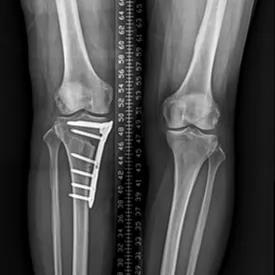

膝关节外科技术力量雄厚,科室配备医护人员30人,其中,主任医师5名,副主任医师3名,主治医师3名,住院医师4名,博士1名,硕士研究生4名。开放床位48张。该科擅长对膝关节严重创伤(包括股骨远端骨折、髌骨骨折、胫骨平台骨折等)、膝骨关节炎阶梯化治疗、保膝治疗、膝关节微创单髁置换术、全膝关节置换术、膝关节翻修术具有丰富的临床诊疗经验,追求微创、无痛、快速康复。对膝关节骨性关节炎采取阶梯化治疗方案,坚持中西并重、内外兼治的原则,取得满意的治疗效果。早期利用中医中药的传统优势,使用中医外治法,例如烫熨治疗、中药涂擦、雷火灸、中药塌渍等,同时辩证内服本院中药制剂及内服方药以及配合西药治疗,开展健康教育,运用运动疗法、物理治疗等辅助支持;中期开展软骨修复、截骨术、单髁置换术、髌股关节置换术等;对于终末期的膝关节OA采用全膝关节置换术。【膝关节外科主要特长】 (一)膝骨关节炎高位截骨术

(五)胫骨平台骨折内固定术